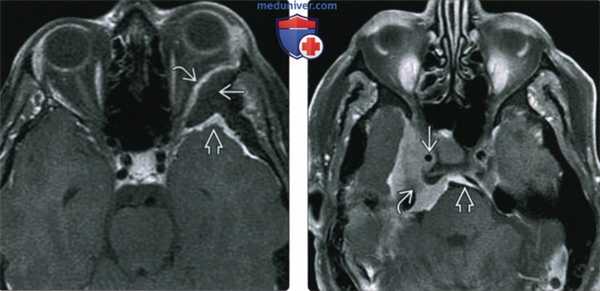

(Слева) При MPT Т1 ВИ FS с КУ в аксиальной проекции у пациента с левосторонним экзофтальмом определяется плоская (en plaque) менингиома левого крыла клиновидной кости: наблюдается выраженный гиперостоз, но виден лишь тонкий контрастный ободок внутри-глазничного и внутричерепного компонентов опухоли.

(Справа) При МРТ Т1 ВИ FS с КУ в ксиальной проекции определяется менингиома среднего отдела основания черепа, окружающая правую внутреннюю сонную артерию и вызывающая сужение последней. Через porus trigeminus опухоль проникает в предмостовую цистерну. С медиальной стороны виден «дуральный хвост».